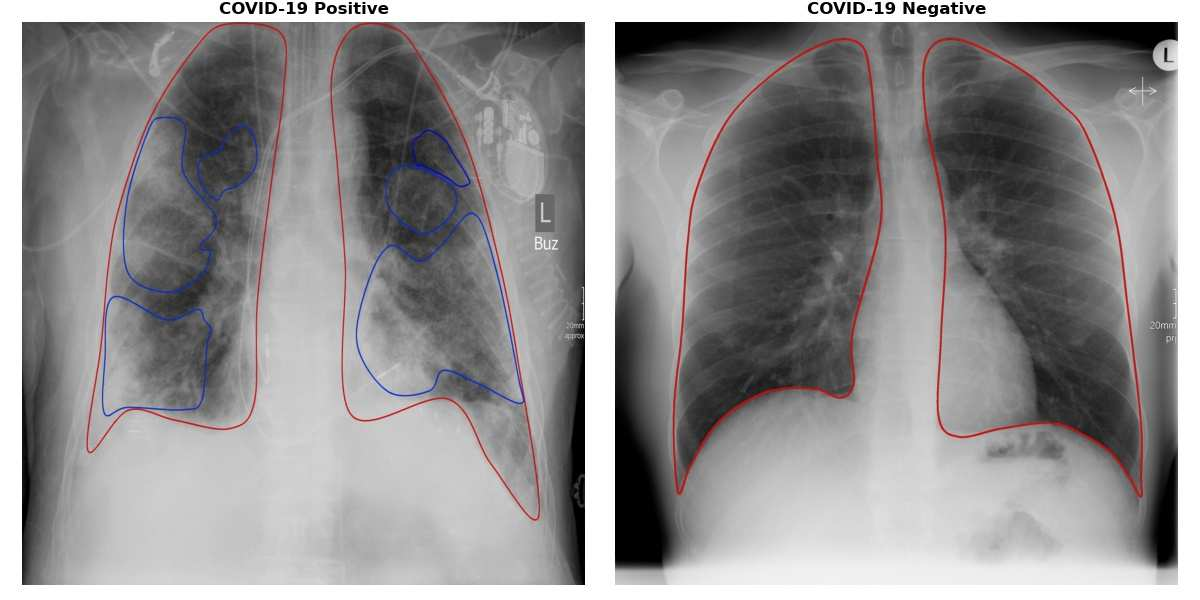

Since the beginning of the COVID-19 pandemic, researchers have developed deep learning models to classify COVID-19 induced pneumonia. As with many medical imaging tasks, the quality and quantity of the available data is often limited. In this work we train a deep learning model on publicly available COVID-19 image data and evaluate the model on local hospital chest X-ray data. The data has been reviewed and labeled by two radiologists to ensure a high quality estimation of the generalization capabilities of the model. Furthermore, we are using a Generative Adversarial Network to generate synthetic X-ray images based on this data. Our results show that using those synthetic images for data augmentation can improve the model's performance significantly. This can be a promising approach for many sparse data domains.